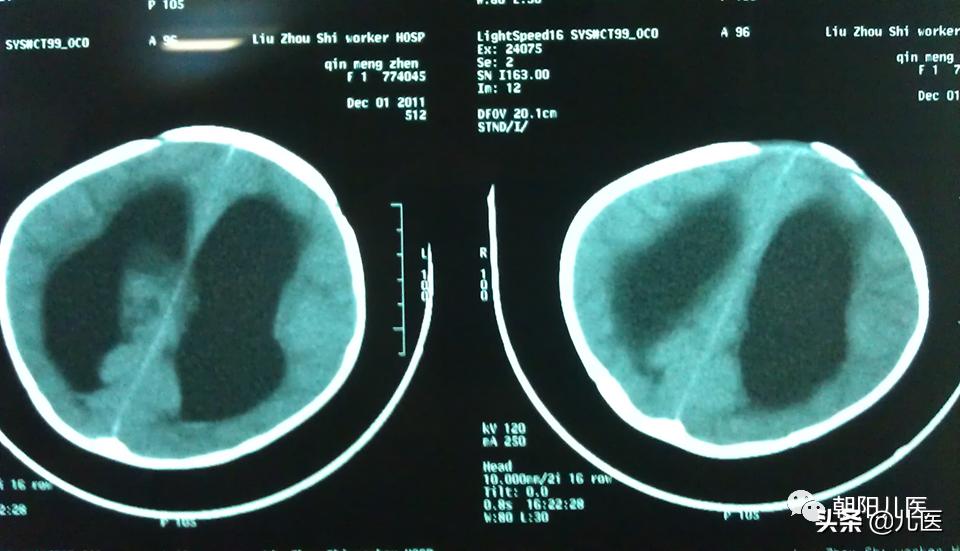

硬膜下积液CT

梗阻性脑积水

定义:是指先天或后天性因素造成的脑脊液循环通路在第四脑室以上受阻,使脑脊液流入蛛网膜下腔的通路发生障碍所引起的病理现象。

特征:脑脊液过多的积聚,导致脑室扩大,颅内压增高,可伴随继发性的脑实质萎缩。